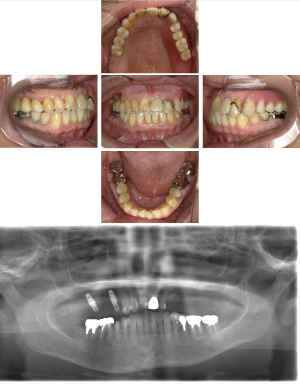

40代 女性 インプラント治療(GBR)

| 年代・性別 | 40代・女性 |

| 主訴 | 硬いものが咬めなくなってきたため、咬めるようになりたい。 |

| 部位 | 右上⑥5④ 右下6 上顎②11② |

| 治療期間 | 約1年2ヶ月 |

| 費用 | ¥2,099,900(税込) |